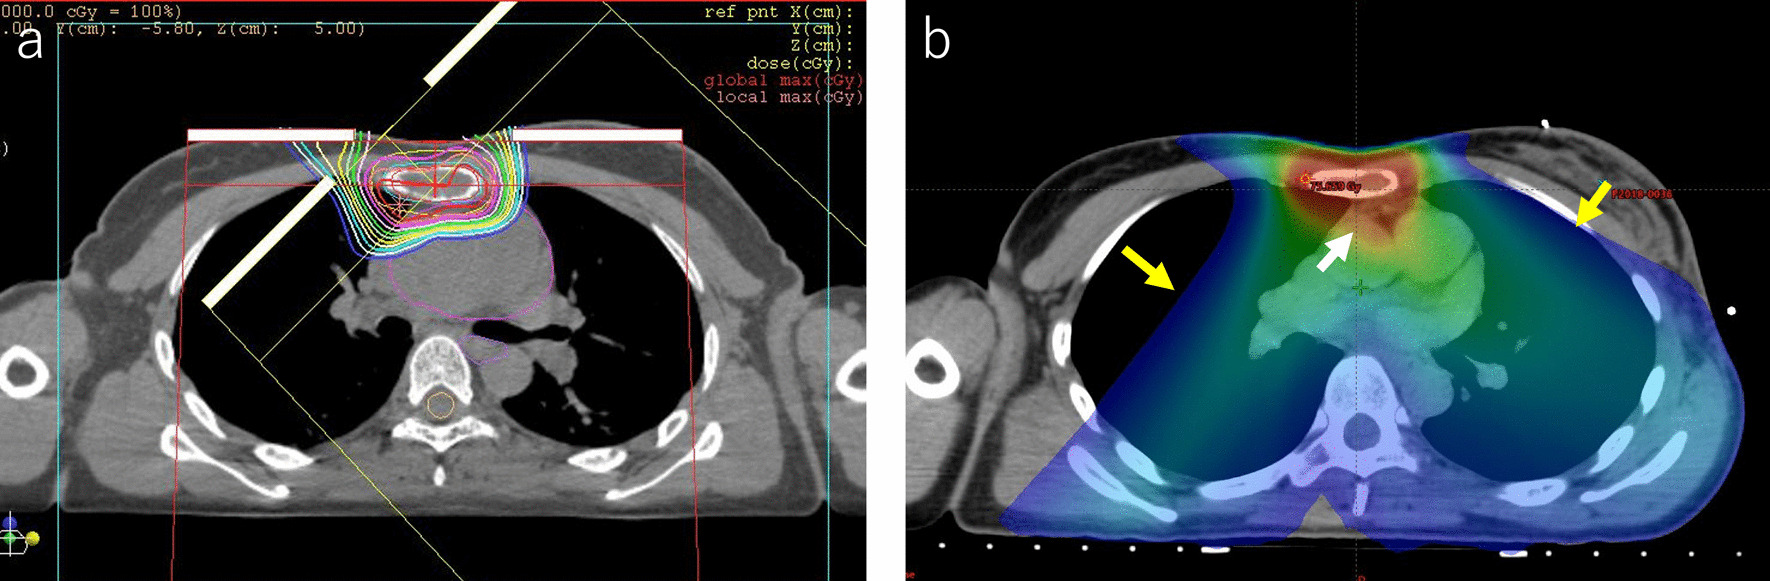

Fig. 5.

Dose distribution for proton beam therapy (a) and photon beam therapy (b). Photon beam therapy shows a dose distribution of 70 Gy in 28 fractions by intensity-modulated radiation therapy (IMRT). With the IMRT, a high-dose area was seen on the heart (white arrow), and a low-dose area was spread to the bilateral lungs (yellow arrow)